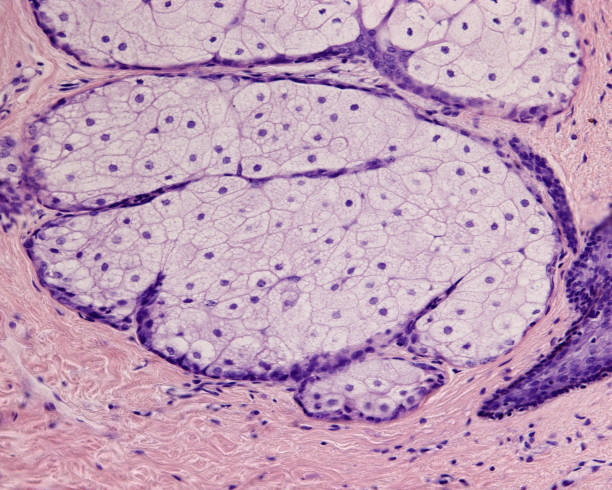

피지낭종

피지낭종은 피지선에서 발생하는 양성 종양으로, 흔히 피부에 발생하나 겨드랑이 등 다른 부위에도 발생할 수 있습니다. 겨드랑이 멍울이 생기는 원인 중 하나가 피지낭종이 있을 수 있습니다. 피지선은 피부 내부에 위치한 유선으로, 피지를 분비하여 피부를 윤활하고 수분을 유지하는 역할을 합니다. 그러나 피지선이 과도하게 분비되거나 피지선의 분비가 차단되면 피지낭종이 발생할 수 있습니다.

겨드랑이 피지낭종은 겨드랑이 부위에서 피지선이 증식하거나 분비에 문제가 생겨서 발생합니다. 이 때, 피지낭종이 크거나 염증이 발생하면 겨드랑이 멍울이 생길 수 있습니다. 피지낭종은 대개 악성종양으로 진행하지 않지만, 큰 크기의 피지낭종이나 발작적인 염증이 발생할 경우에는 불편함을 유발할 수 있기 때문에 치료가 필요할 수 있습니다.